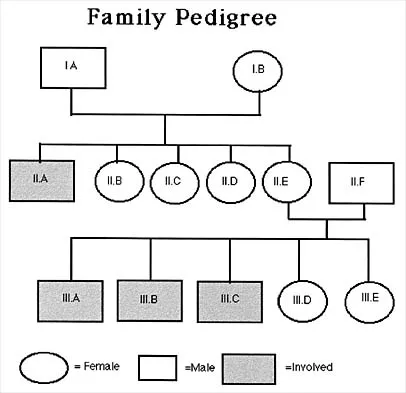

Question 96

Figure 53 shows the pedigree of a family with an unusual type of muscular dystrophy. This pedigree is most consistent with what type of inheritance pattern?

Explanation